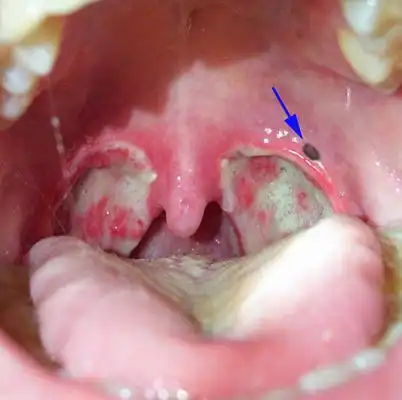

扁桃体结石图片50